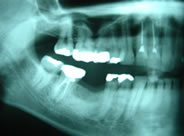

下顎右側の臼歯2本がありません

初診時のX線像です

2本のインプラントを埋入しました

手術後のX線像です

2本の白いセラミック冠が入りました

入れ歯でなく自分の歯と同じように噛めるようになりました

リコール時のX線像です